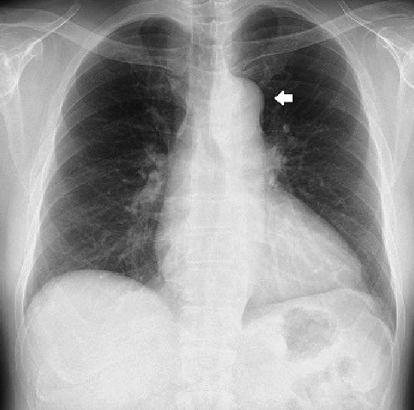

胸部X線

心胸郭比53%,左側大動脈弓陰影の突出を認めた(Fig. 1).

Fig. 1 Chest X-ray showing the prominence of the left first cardiac arch due to ductus arteriosus aneurysm (DAA) (white arrow)